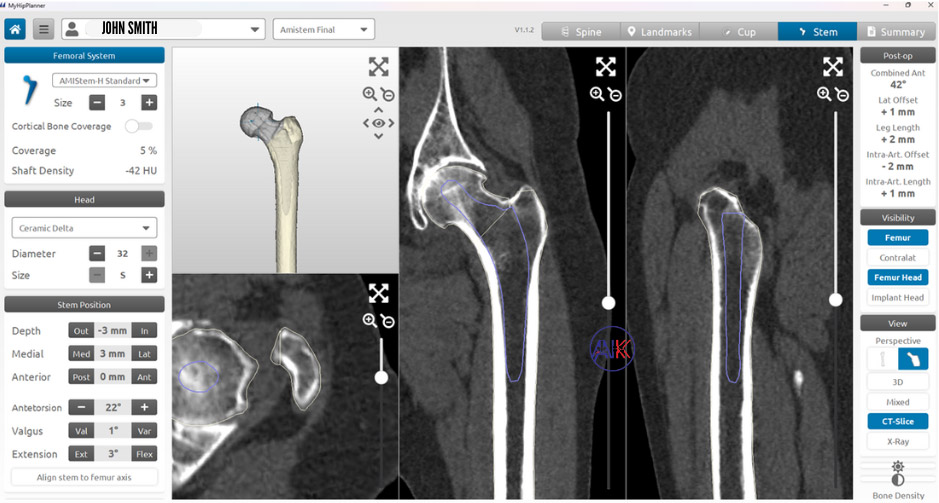

3D Preoperative Planning Technology: Prior to surgery, your will undergo CT or MRI scanning of your hip, leading to the creation of a 3D reconstruction, tailored to Dr Keeley’s specifications. This model facilitates the production of personalised surgical instruments for use in your operation.

In-Surgery Advanced Imaging and Software: Employing state-of-the-art imaging, computer software, and navigation systems, Dr Keeley achieves unprecedented precision in prosthetic component placement. The use of intraoperative X-Rays further guides the accuracy of the surgical process, underscoring Dr Keeley’s commitment to leveraging technological advancements for optimal patient outcomes.

Dr Keeley incorporates advanced navigation tools intra-operatively to assist in accurately positioning and aligning the implants. Patient-specific instrumentation, like MyHip, may also be used to customise the procedure to your individual anatomy. A verifier tool may also be employed to confirm the proper fit and positioning of the implants, ensuring optimal stability and functionality of the new joint.